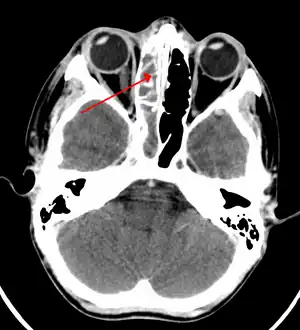

Maxillary sinusitis caused by a dental infection associated with periorbital cellulitis -